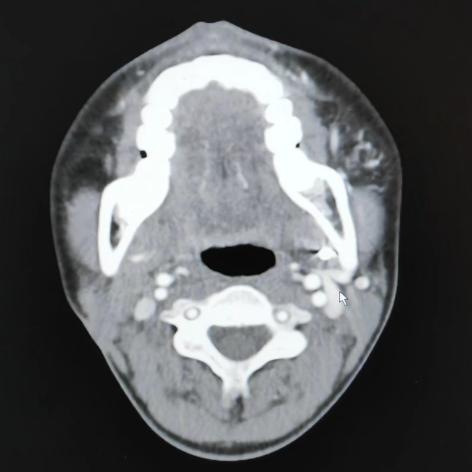

2.增强CT是可疑颌骨中心性血管瘤病变的首要辅助检查手段,颌骨骨髓腔内动脉性强化的血管团块是颌骨中心性血管瘤的特征性表现。此外,在颌骨动静脉畸形患者的头颈部增强CT中,可观察到患侧颈外静脉较对侧增粗的现象,提示病变侧出现静脉系统压力增高的血流动力学状态,可反映病变区动静脉瘘瘘口情况。

左下颌骨中心性血管瘤患者的头颈部增强CT显示颈外静脉增粗(箭头)